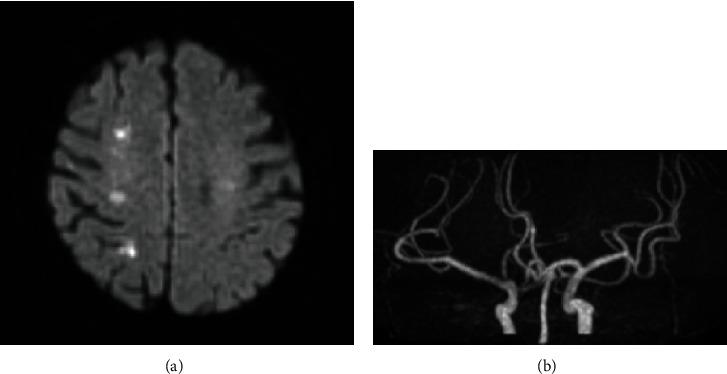

We report a case of gastrointestinal stromal tumor (GIST) with repeated multiple cerebral infarctions mimicking ovarian cancer. A 79-year-old postmenopausal woman had multiple cerebral infarctions with a giant pelvic tumor detected by computed tomography. Ovarian cancer with Trousseau's syndrome was suspected. Through laparoscopic biopsy on the tumor surface, she was diagnosed with left ovarian fibrosarcoma; although, the abdominal cavity could not be observed appropriately. Ovarian fibrosarcoma is an extremely rare tumor and still has no adequate treatment strategy. Complete resection was planned. The tumor was extremely fragile, and gelatinous that it easily bled. Meanwhile, the uterus and bilateral ovaries and fallopian tubes were all normal. The tumor invaded only the peritoneum near the left sacral uterine ligament and sigmoid colon, with no peritoneal dissemination. To completely remove the tumor, we performed total hysterectomy with bilateral salpingo-oophorectomy and omentectomy and sigmoidal and rectal resection with colostomy. Despite resuming her anticoagulant therapy on postoperative day 4, she had recurrent multiple strokes. On histopathological examination, tumor showed spindle cell proliferation with severe atypia, increased mitotic activity, and widespread necrosis. Immunohistochemical studies showed positive staining for c-kit, CD34, and DOG1. Thus, she was diagnosed with GIST. This case was rare and highly malignant, with a high risk of recurrence of GIST because of a giant ruptured tumor that had a mitotic activity of 36/10 high-power fields from the sigmoid colon. Multiple cerebral infarctions mimicking ovarian cancer recurred. Therefore, preoperative diagnosis of an atypical GIST was extremely difficult.

我们报告一例胃肠道间质瘤(GIST),其表现为反复多次脑梗死,酷似卵巢癌。一名79岁的绝经后女性出现多次脑梗死,计算机断层扫描发现盆腔有一个巨大肿瘤。怀疑为伴有特鲁索综合征的卵巢癌。通过对肿瘤表面进行腹腔镜活检,诊断为左卵巢纤维肉瘤;不过,腹腔观察并不充分。卵巢纤维肉瘤是一种极其罕见的肿瘤,目前仍没有足够的治疗策略。计划进行完整切除。肿瘤极其脆弱,质地呈胶冻状,极易出血。同时,子宫及双侧卵巢和输卵管均正常。肿瘤仅侵犯左骶子宫韧带和乙状结肠附近的腹膜,无腹膜播散。为完全切除肿瘤,我们进行了全子宫切除术、双侧输卵管卵巢切除术、大网膜切除术以及乙状结肠和直肠切除术并做了结肠造口术。尽管术后第4天恢复了抗凝治疗,但她仍反复出现多次中风。组织病理学检查显示肿瘤呈梭形细胞增殖,具有严重异型性、有丝分裂活性增加及广泛坏死。免疫组化研究显示c-kit、CD34和DOG1呈阳性染色。因此,她被诊断为GIST。该病例罕见且恶性程度高,由于肿瘤巨大且破裂,乙状结肠高倍视野下有丝分裂活性为36/10,GIST复发风险高。酷似卵巢癌的多次脑梗死复发。因此,术前诊断非典型GIST极其困难。